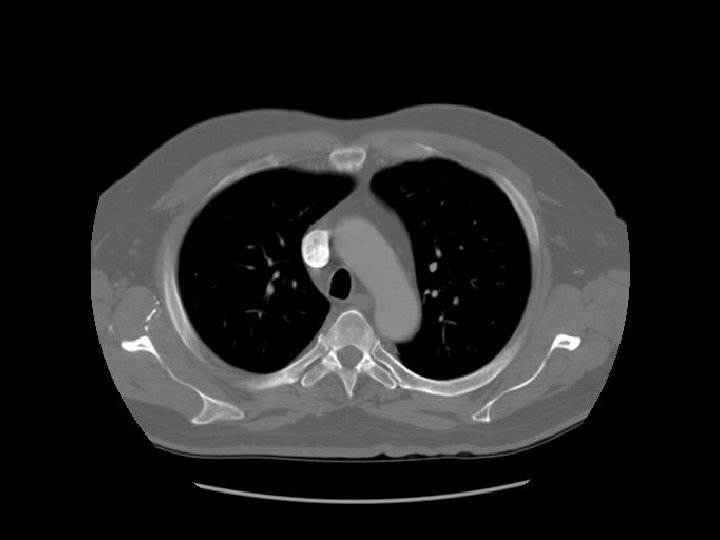

Ascending aorta Main pulmonary artery Descending aorta